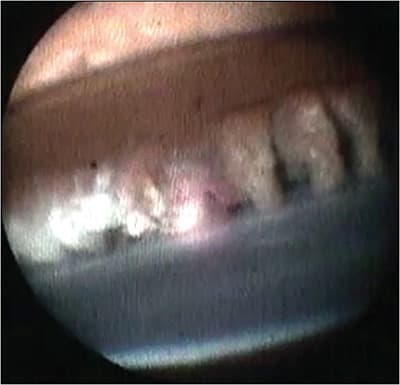

Endoscopic cyclophotocoagulation (ECP) surgery for glaucoma lowers intraocular pressure (IOP) by decreasing aqueous production via direct laser treatment of the ciliary processes.1 Endoscopic cyclophotocoagulation was initially developed by Martin Uram in 1992,2 and it uses a single intraocular Endo Optiks probe (BVI) combining a diode endolaser, aiming beam, light source, and endoscope (Figure 1). Direct visualization and titration of power allow for controlled, targeted ablation of the ciliary process, which reduces collateral tissue damage (Figures 2 and 3).1 Histologic studies have shown that tissue injury is limited to the ciliary processes and associated capillary bed, sparing the ciliary muscle and stromal tissue.3